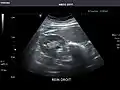

Aorta -

Aorta: Visualized portions normal in caliber, 16 x 15 mm.